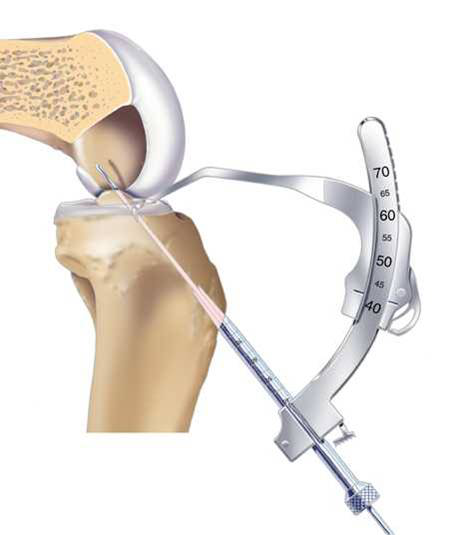

Rigidfix-Intrafix 固定。Rigidfix為PLLA可吸收螺釘。Intrafix是將擠壓釘置于釘鞘內(nèi),防止螺釘對移植物的直接損傷,同時達到360度固定,其材料為CP/PLA,具有誘導成骨和可吸收性

關節(jié)鏡手術專用器械

Rigidfix固定

Intrafix固定